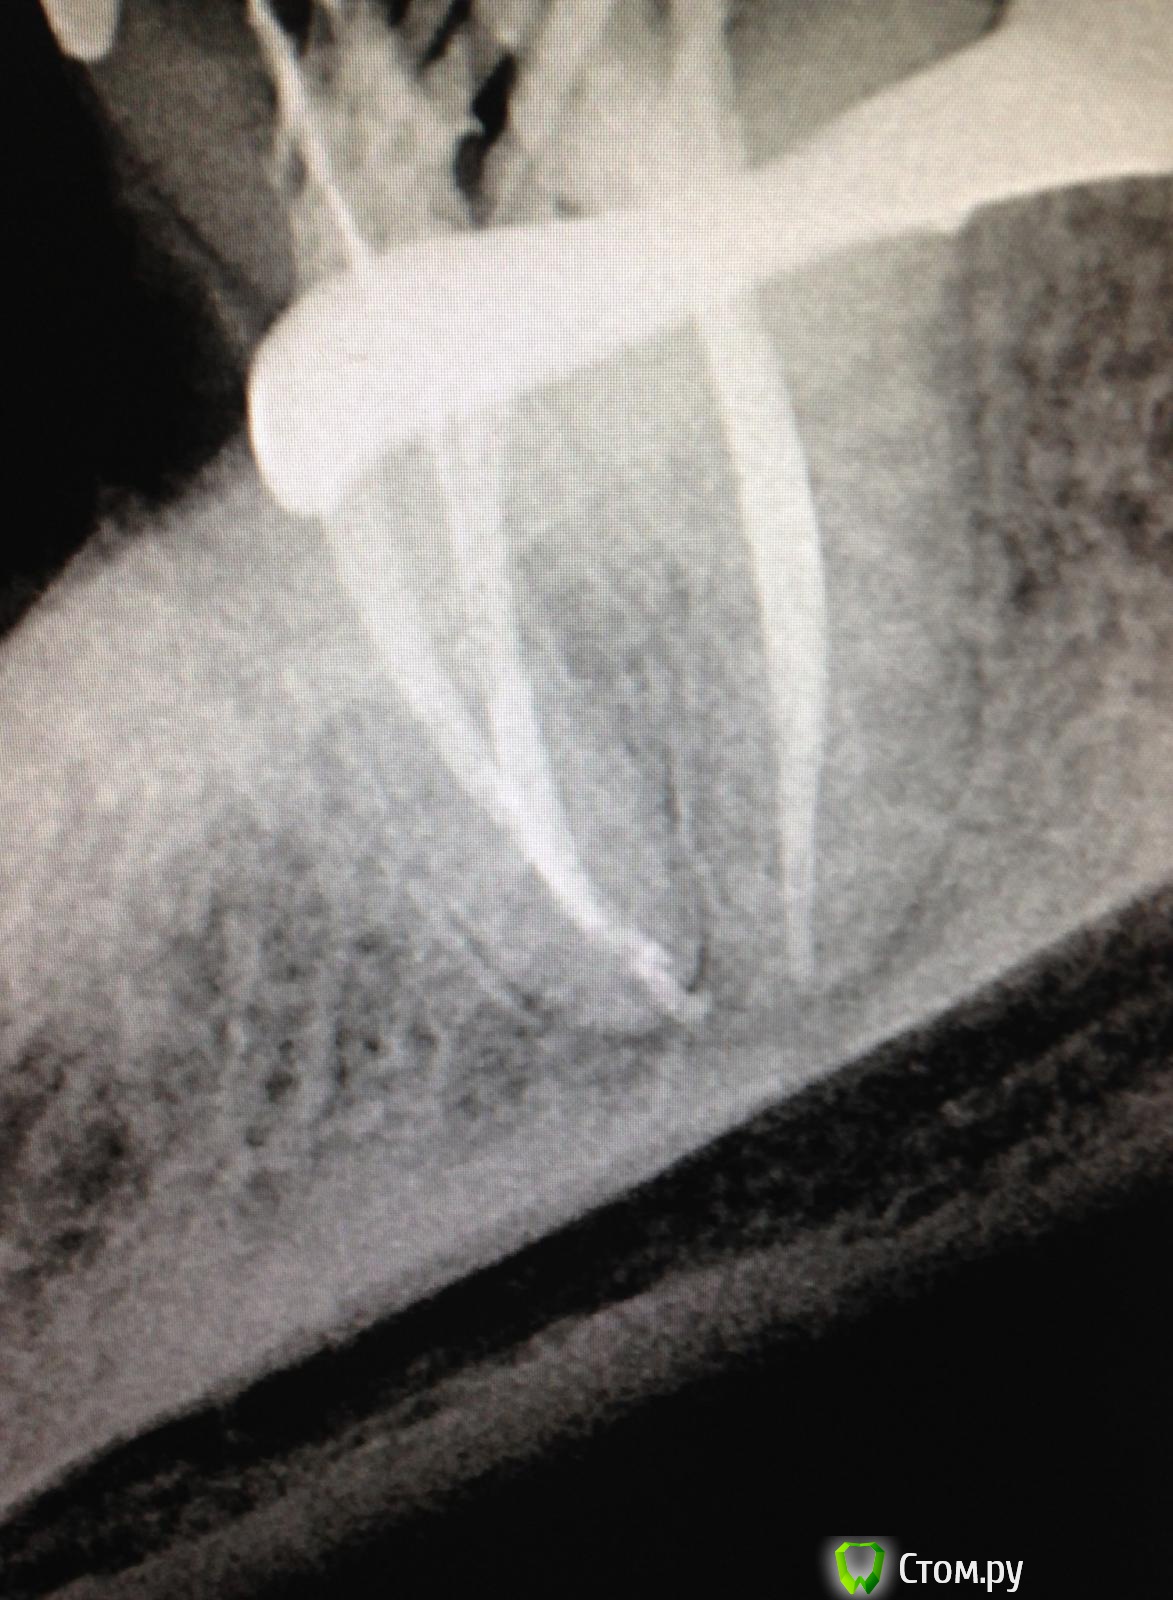

SSTi Опубликовано 22 августа, 2014 Автор Поделиться Опубликовано 22 августа, 2014 16. Резорцин. Убрал пломбу цементную, в небном наполовину пусто. Другие надо искать. В первый визит - коффер, уз аккуратно поездили по дну. Откопали мб. 15ка на 1 мм заходила. Полностью обработал небный и прошел на 2/3 мб. Кальций. Второй визит - коффер, нашел дб и мб2(сходится с мб через 3-4 мм). Расширились. Помылись. Ломанули профайл 20.04 в дб, обошли, помыли еще, озвучили и достали. латералка. Не идеально. Но для рф и это прекрасно. 1 Ссылка на комментарий

SSTi Опубликовано 22 августа, 2014 Автор Поделиться Опубликовано 22 августа, 2014 (изменено) Нормально) я бы отломок только часа два доставал) Где сломался?В дистальном в средней трети. Да его легко было обойти. Потом подцепил чуть и вымыл. Даже не успел огорчиться Изменено 22 августа, 2014 пользователем SSTi Ссылка на комментарий

SSTi Опубликовано 25 августа, 2014 Автор Поделиться Опубликовано 25 августа, 2014 Найдите фэйл))) 37 Ссылка на комментарий

SSTi Опубликовано 25 августа, 2014 Автор Поделиться Опубликовано 25 августа, 2014 В мя грохнул Неа) ничего не сломал. Медиальные сходятся за 2 мм до апекса) Ссылка на комментарий

SSTi Опубликовано 25 августа, 2014 Автор Поделиться Опубликовано 25 августа, 2014 (изменено) Ладно. Ответ - выход мш в дистальном на 1мм от упора. А все дело в том, что сформировал стопупор 40.02. Открываю свой чудо ящик, ищу гутту 40.02 , ищу , ищу , ищу... А она кончилась. Ассорти от 45 и выше кончились. Пришлось брать 35.02. ... Только моя дурная голова потом додумалась, что надо было просто обрезать чуть штифт и все. Хвост отпаянный измерил - короче на 1 мм , чем должен был быть. Одно душу греет - мылись мы как никогда. Изменено 25 августа, 2014 пользователем SSTi 1 Ссылка на комментарий